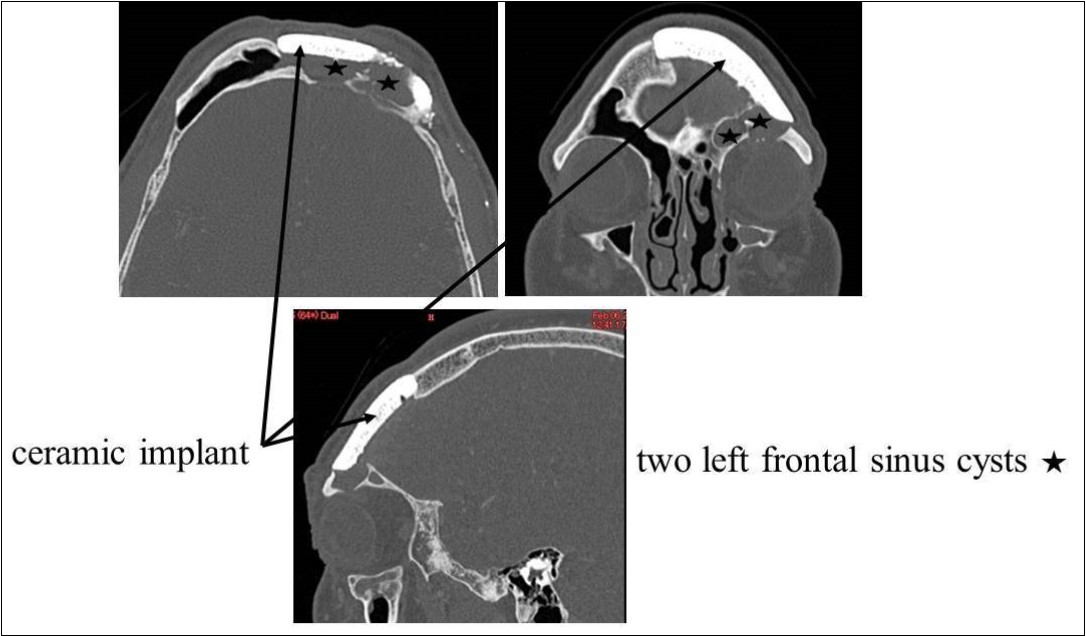

Recurrent frontal sinusitis was suspected, and the patient was referred to our department for evaluation on February 14, 2007. On initial evaluation, the left upper eyelid swelling was resolved; however, paranasal sinus computed tomography (CT) showed two left frontal sinus cysts (Figure 1). The patient had a history of hypertension that was well-controlled on oral medications. No other major disorders were present, including diabetes or heart disease.

Figure 1.CT of the paranasal sinuses showed two left frontal sinus cysts. Black arrows: ceramic implant. Black stars: two left frontal sinus cysts

CT of the paranasal sinuses showed two left frontal sinus cysts. Black arrows: ceramic implant. Black stars: two left frontal sinus cysts

On April 16, 2008, reoperation was performed to place a ceramic implant, but some pus was found in the left lateral sinus. The lesion was debrided, the dead space was filled with muscle, and surgery was completed without ceramic implantation. On October 17, 2008, another surgery confirmed that the frontal sinus was clean, and a ceramic implant was placed. The postoperative course has been good, and as of May 2009, the frontal sinus extending laterally is filled with air (Figure 5, Figure 6).

Figure 5.Paranasal sinus CT after the last surgery. White star: The frontal sinus extending laterally is filled with air.

Paranasal sinus CT after the last surgery. White star: The frontal sinus extending laterally is filled with air.